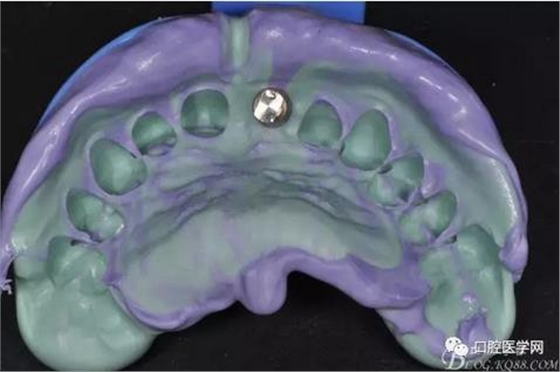

圖12 硅橡膠取模